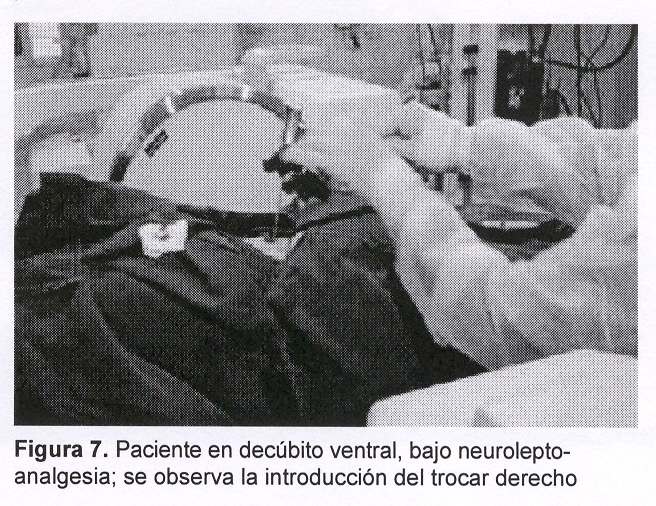

Sexo femenino, 43 años, con cuadro de 45 días de evolución dado por dolor raquídeo lumbar intenso, de comienzo súbito y evolución progresiva a pesar del tratamiento médico. Al igual que en el caso anterior el dolor era tan intenso que la obligaba a mantener reposo absoluto en cama. Al examen físico presentaba intenso dolor raquídeo a la palpación de L3, sin signología radicular ni deficitaria. Fue estudiada con radiografía simple (figura 5) y TC de columna lumbosacra que mostraban: aplastamiento del cuerpo vertebral de L3 a predominio de la plataforma inferior y falta de definición del pedículo derecho, múltiples imágenes líticas a nivel del cuerpo y del pedículo derecho con lisis parcial del muro posterior, abombamiento hacia el canal raquídeo (figura 6). Existían, además, otras imágenes líticas a nivel costal a la altura de la undécima costilla derecha. Las imágenes correspondían a sustitución ósea por metástasis. En esta paciente no existía noción de tumor primitivo por lo cual se planteó la realización de biopsia de la lesión concomitantemente con el tratamiento mediante vertebroplastia percutánea (figuras 7 y 8).